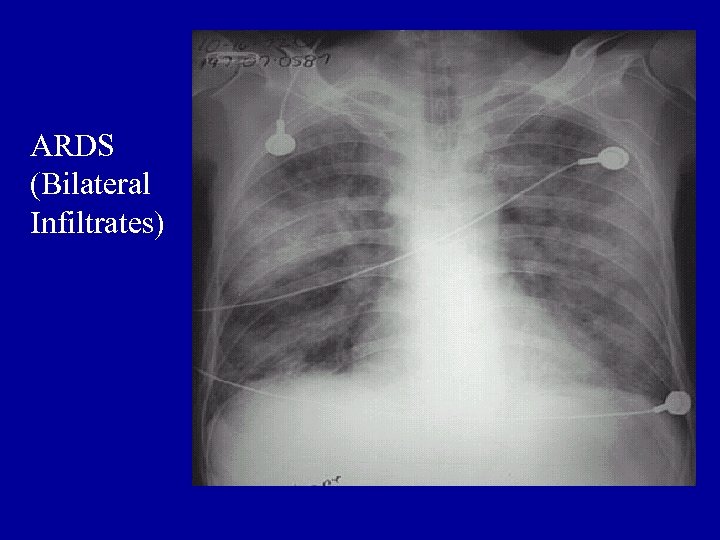

Other Laboratory Findings in ARF CXR Abnormalities Complete Blood Count (look at WBC and Hgb, which may suggest chronic hypoxia) Electrolyte Abnormalities (look at bicarbonate)

ARDS (Bilateral Infiltrates)